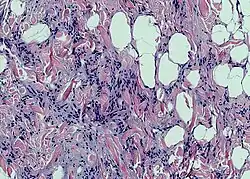

Photomicrograph of a spindle cell lipoma.

According to histology, the lesion is made up of tiny, homogeneous spindle cells and mature adipocytes combined with eosinophilic collagen bundles inside a myxoidstroma. According to immunohistochemical staining, the spindle cells are positive for CD34 but negative for S-100 protein.[3]